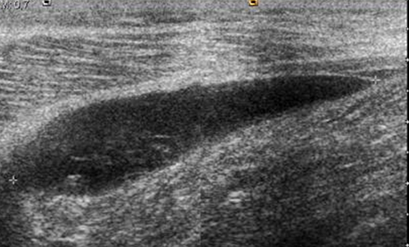

Se identifica en la ecografía, como una lesión posterior y comunicada en la cavidad articular. Puede tener contenido anecoico, hipoecoico o de ecogenicidad mixta y se relaciona con los músculos. (9). (Fig 175A y 175B).

Fig 175 A. Quiste de Baker.

Ecografía sagital. Imagen ovalada y de consistencia quística, en la fosa poplítea. Muestra ecos en su interior por inflamación o alto contenido de proteínas.